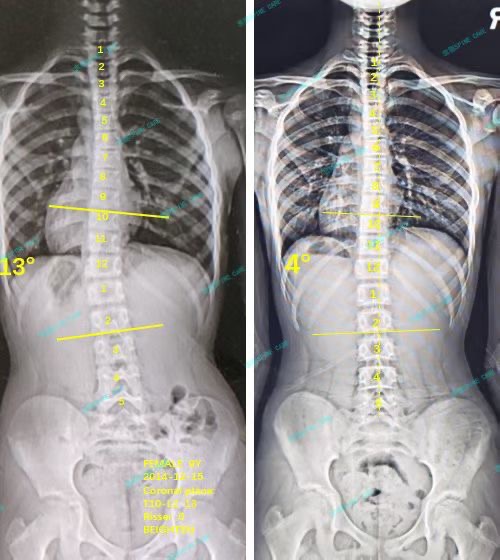

衷德脊柱,我们只关注侧弯保守治疗~

Zhongde Spine, bending no breaking ~